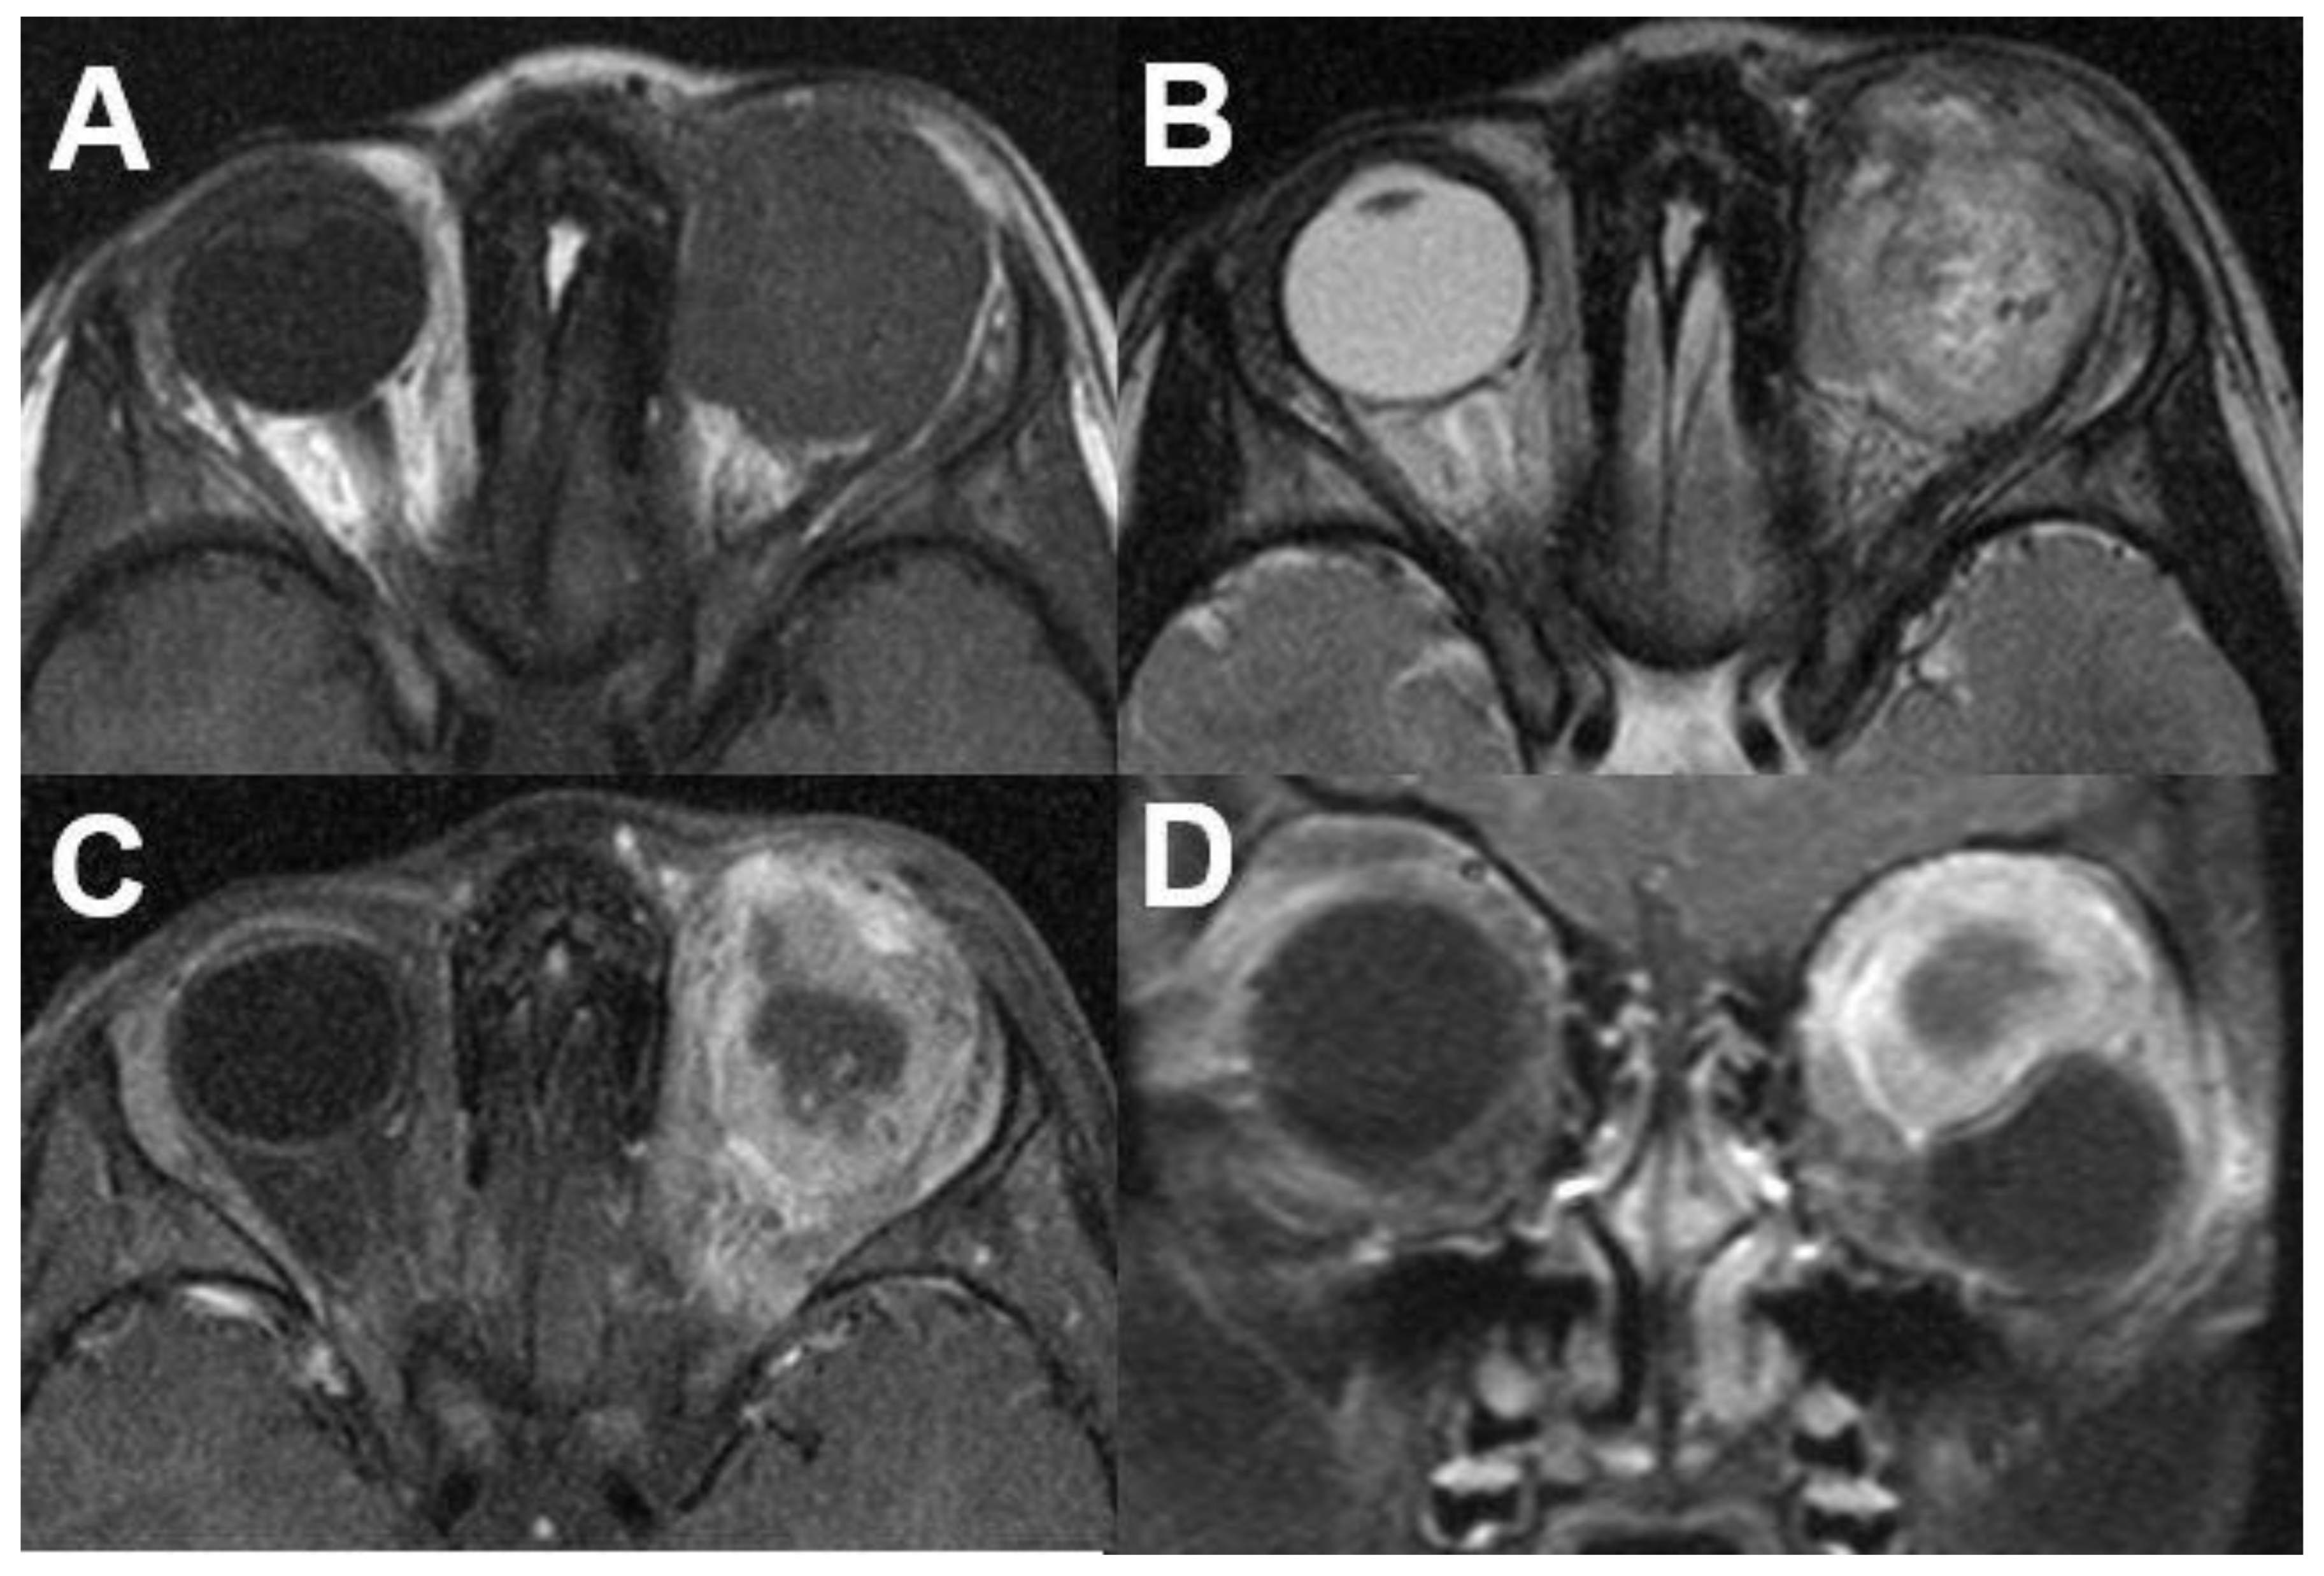

3.1. Intraocular Tumors

3.1.1. Retinoblastoma

3.1.2. Uveal Melanoma